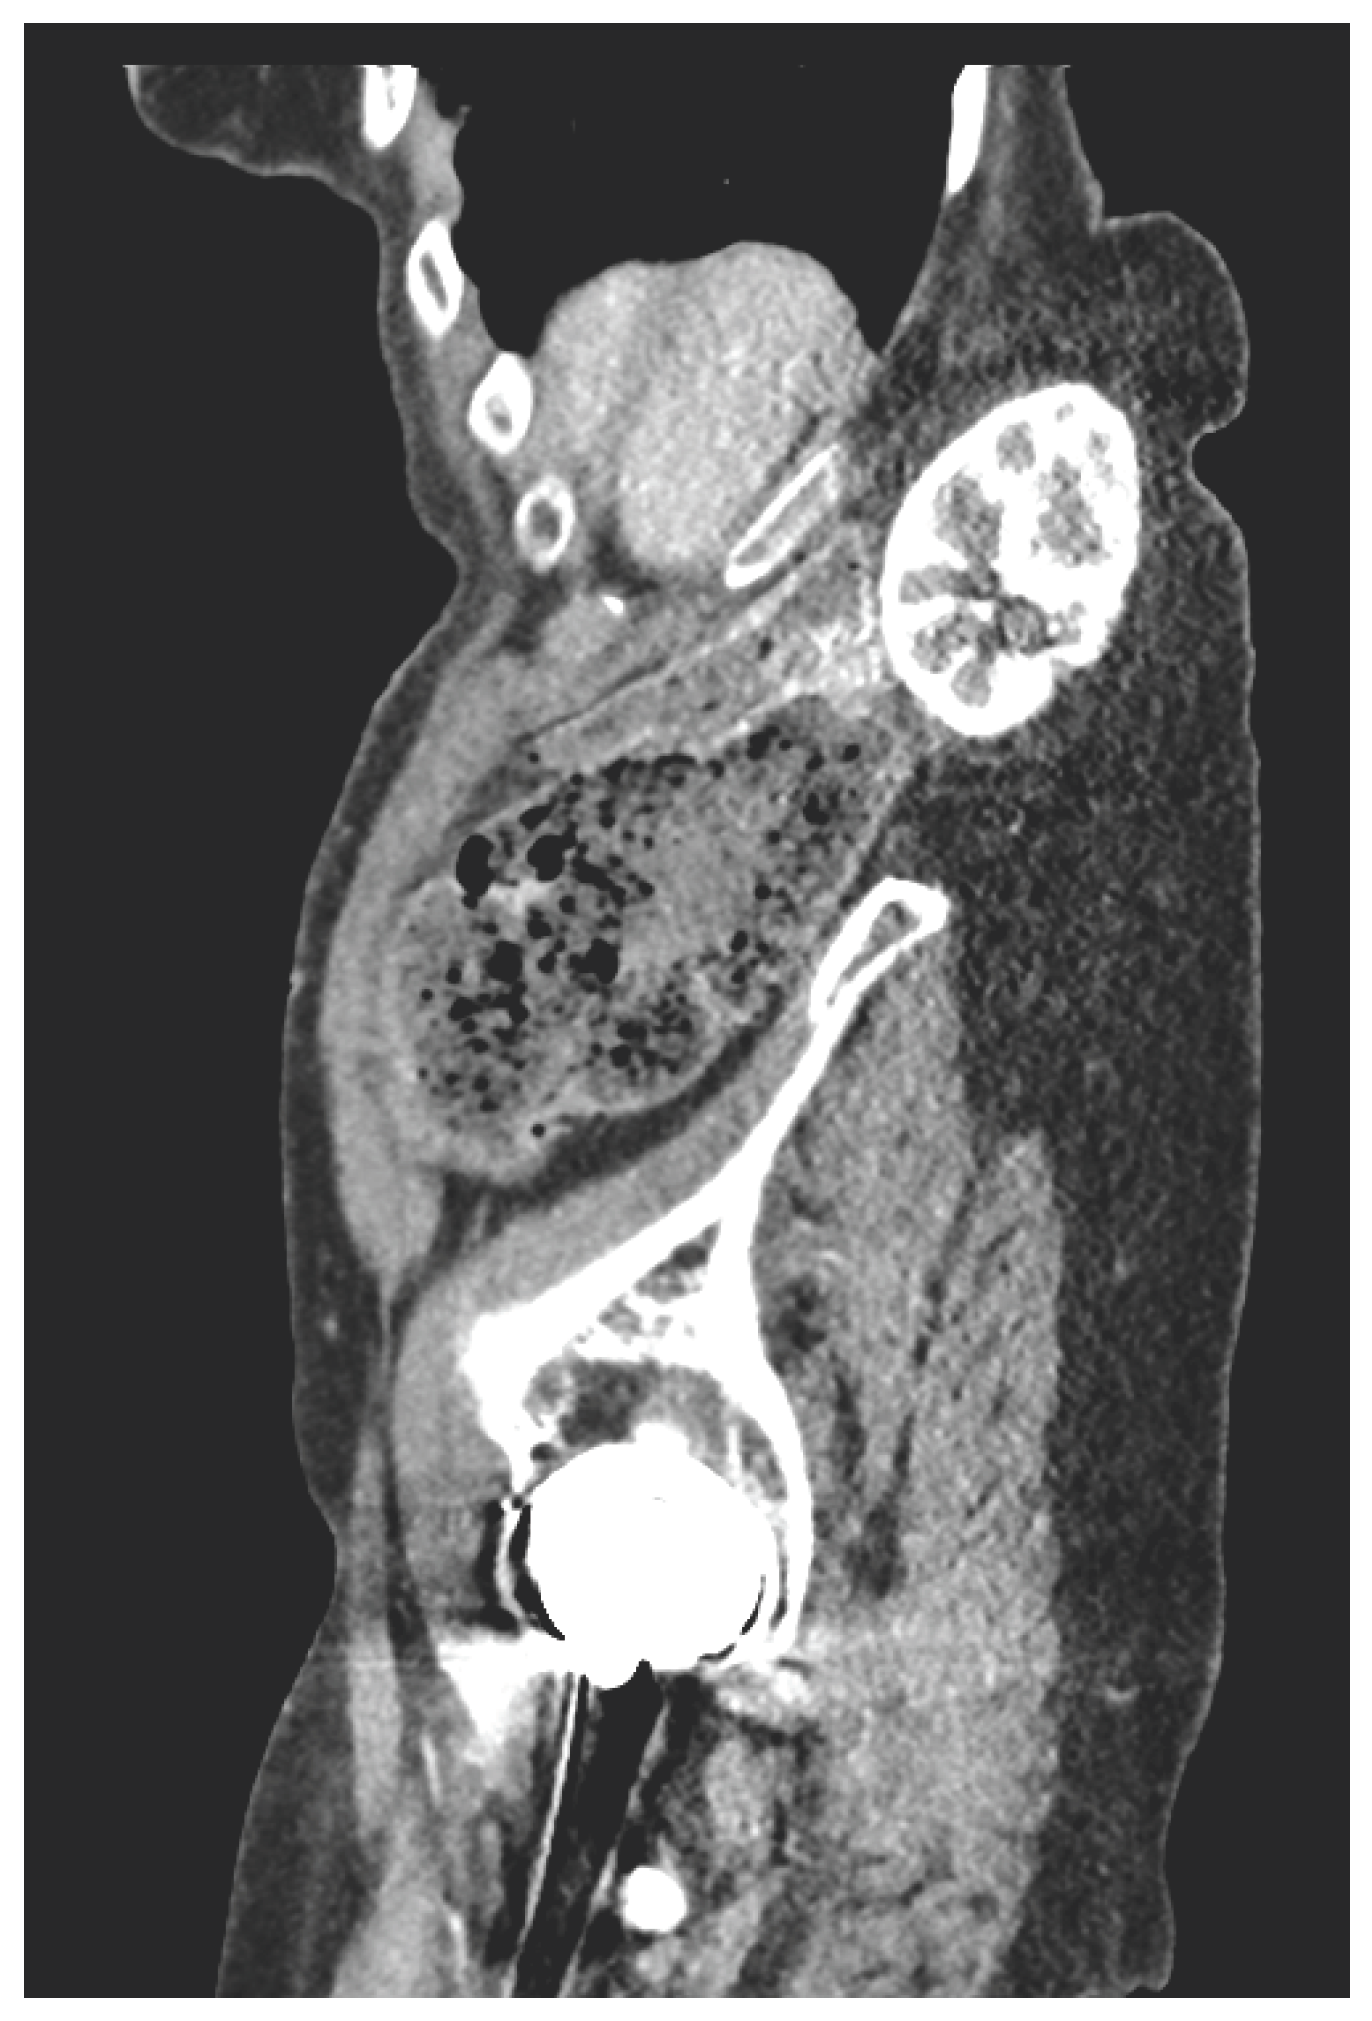

Biochemistry and inf lammatory markers were normal. CT imaging demonstrated a right renal flank hernia through the retroperitoneum into the subcutaeneous tissue (Figure 1A,B). The renal artery and vein were significantly stretched, without evidence of acute pathology. There was no evidence of hydronephrosis or delayed nephrogram.

Figure 1.

A. Axial CT. B. Sagittal CT.